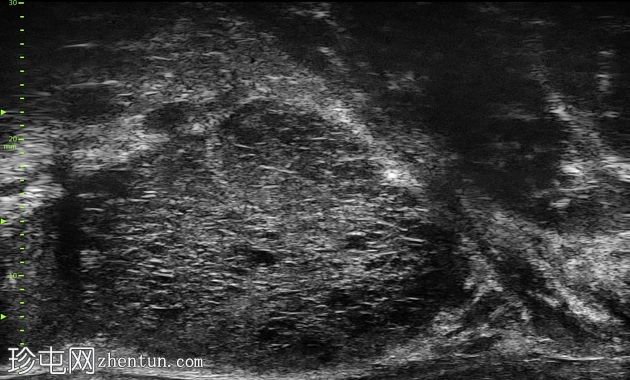

显微超声

1.png

超声

右侧旁矢状切面

尖部至中部

左侧旁矢状切面

尖部内侧

左侧尖部内侧呈“瑞士奶酪”样改变,无内部强回声或局灶性离散病灶。右侧尖部至中部可见一离散结节,内含混合回声病灶及不规则声影。

左侧尖部内侧的显微超声图像符合PRI-MUS 2级,提示前列腺癌风险较低。右侧尖部至中部的显微超声图像符合PRI-MUS 5级,提示前列腺癌风险极高。已对该区域进行靶向活检。

活检样本送至病理科进行检查,证实右侧前列腺为 4 级(Gleason 评分 4+4)腺癌。